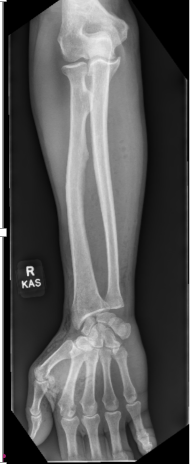

A “Delayed Jersey Finger”: Case Report and Literature Review

Musa Ergin , Süha Ahmet Aktaş